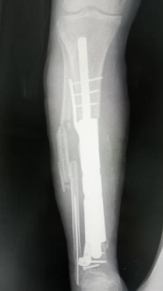

在3D打印的金属假体完成后,吴大爷再次入院。2025年12月周翔教授再次亲临我院指导手术,经过掀起原移植的皮瓣,取出临时植入的骨水泥及固定的钢板,在胫骨远近端进行精准截骨,顺利安装好3D打印的胫骨金属假体。不到2小时,即按术前规划成功完成了这个“私人定制”式的手术。

△3D打印定制式胫骨金属假体(可拆分)。